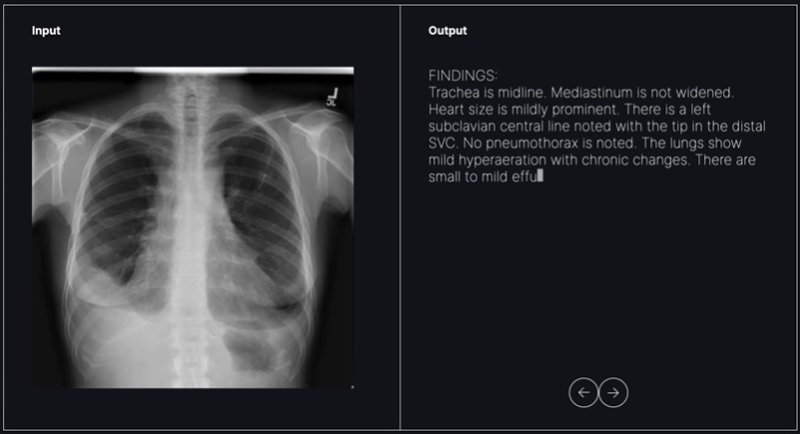

숨빗AI가 개발 중인 영상의학과용 초기 판독문 생성 솔루션 'AI리드-CXR' 활용 모습.(숨빗AI 제공)/뉴스1 ⓒ News1

숨빗AI는 영상의학과 의사를 위한 AI 기반 초안 판독문 생성 솔루션 'AI리드-CXR'(AIRead-CXR)을 개발하고 있다. 생성형 AI 기반인 AI리드-CXR은 흉부 X-레이(CXR)에서 탐지해야 할 다양한 소견에 대한 개인화된 초안 판독문과 비정상 가능성을 제공해 영상의학과 의사들이 더욱 빠르고 정확하게 영상 판독을 할 수 있도록 돕는 것을 목표로 한다.